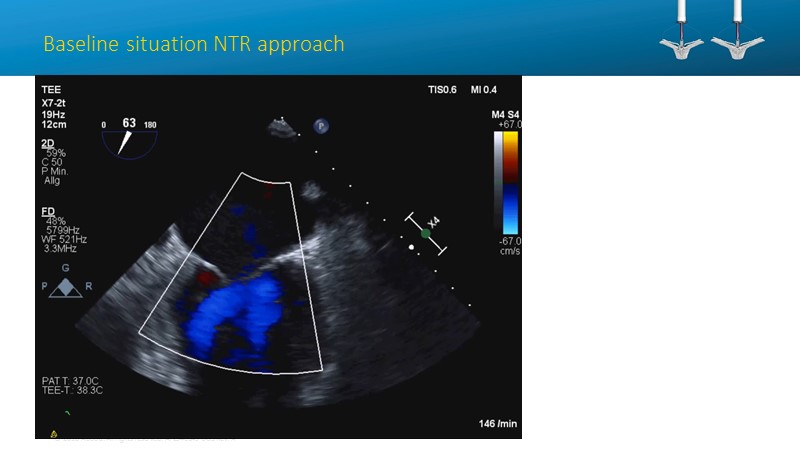

- To learn how will product innovation (Mitraclip NTR / XTR) drive improvement in procedural and clinical outcomes (EXPAND)